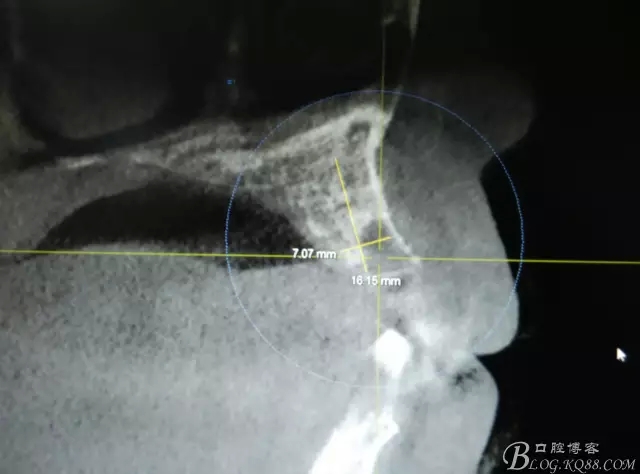

患者、楊xx、男、49歲。主訴:左側(cè)前牙拔除半年,活動(dòng)義齒修復(fù)四個(gè)月,要求種植修復(fù)。??茩z查:21缺失,牙槽粘膜厚度正常。CBCT檢查:高度16mm,寬度7mm.術(shù)前簽知情同意書。

圖2.CBCT的三維成像及縱剖面、水平面影像